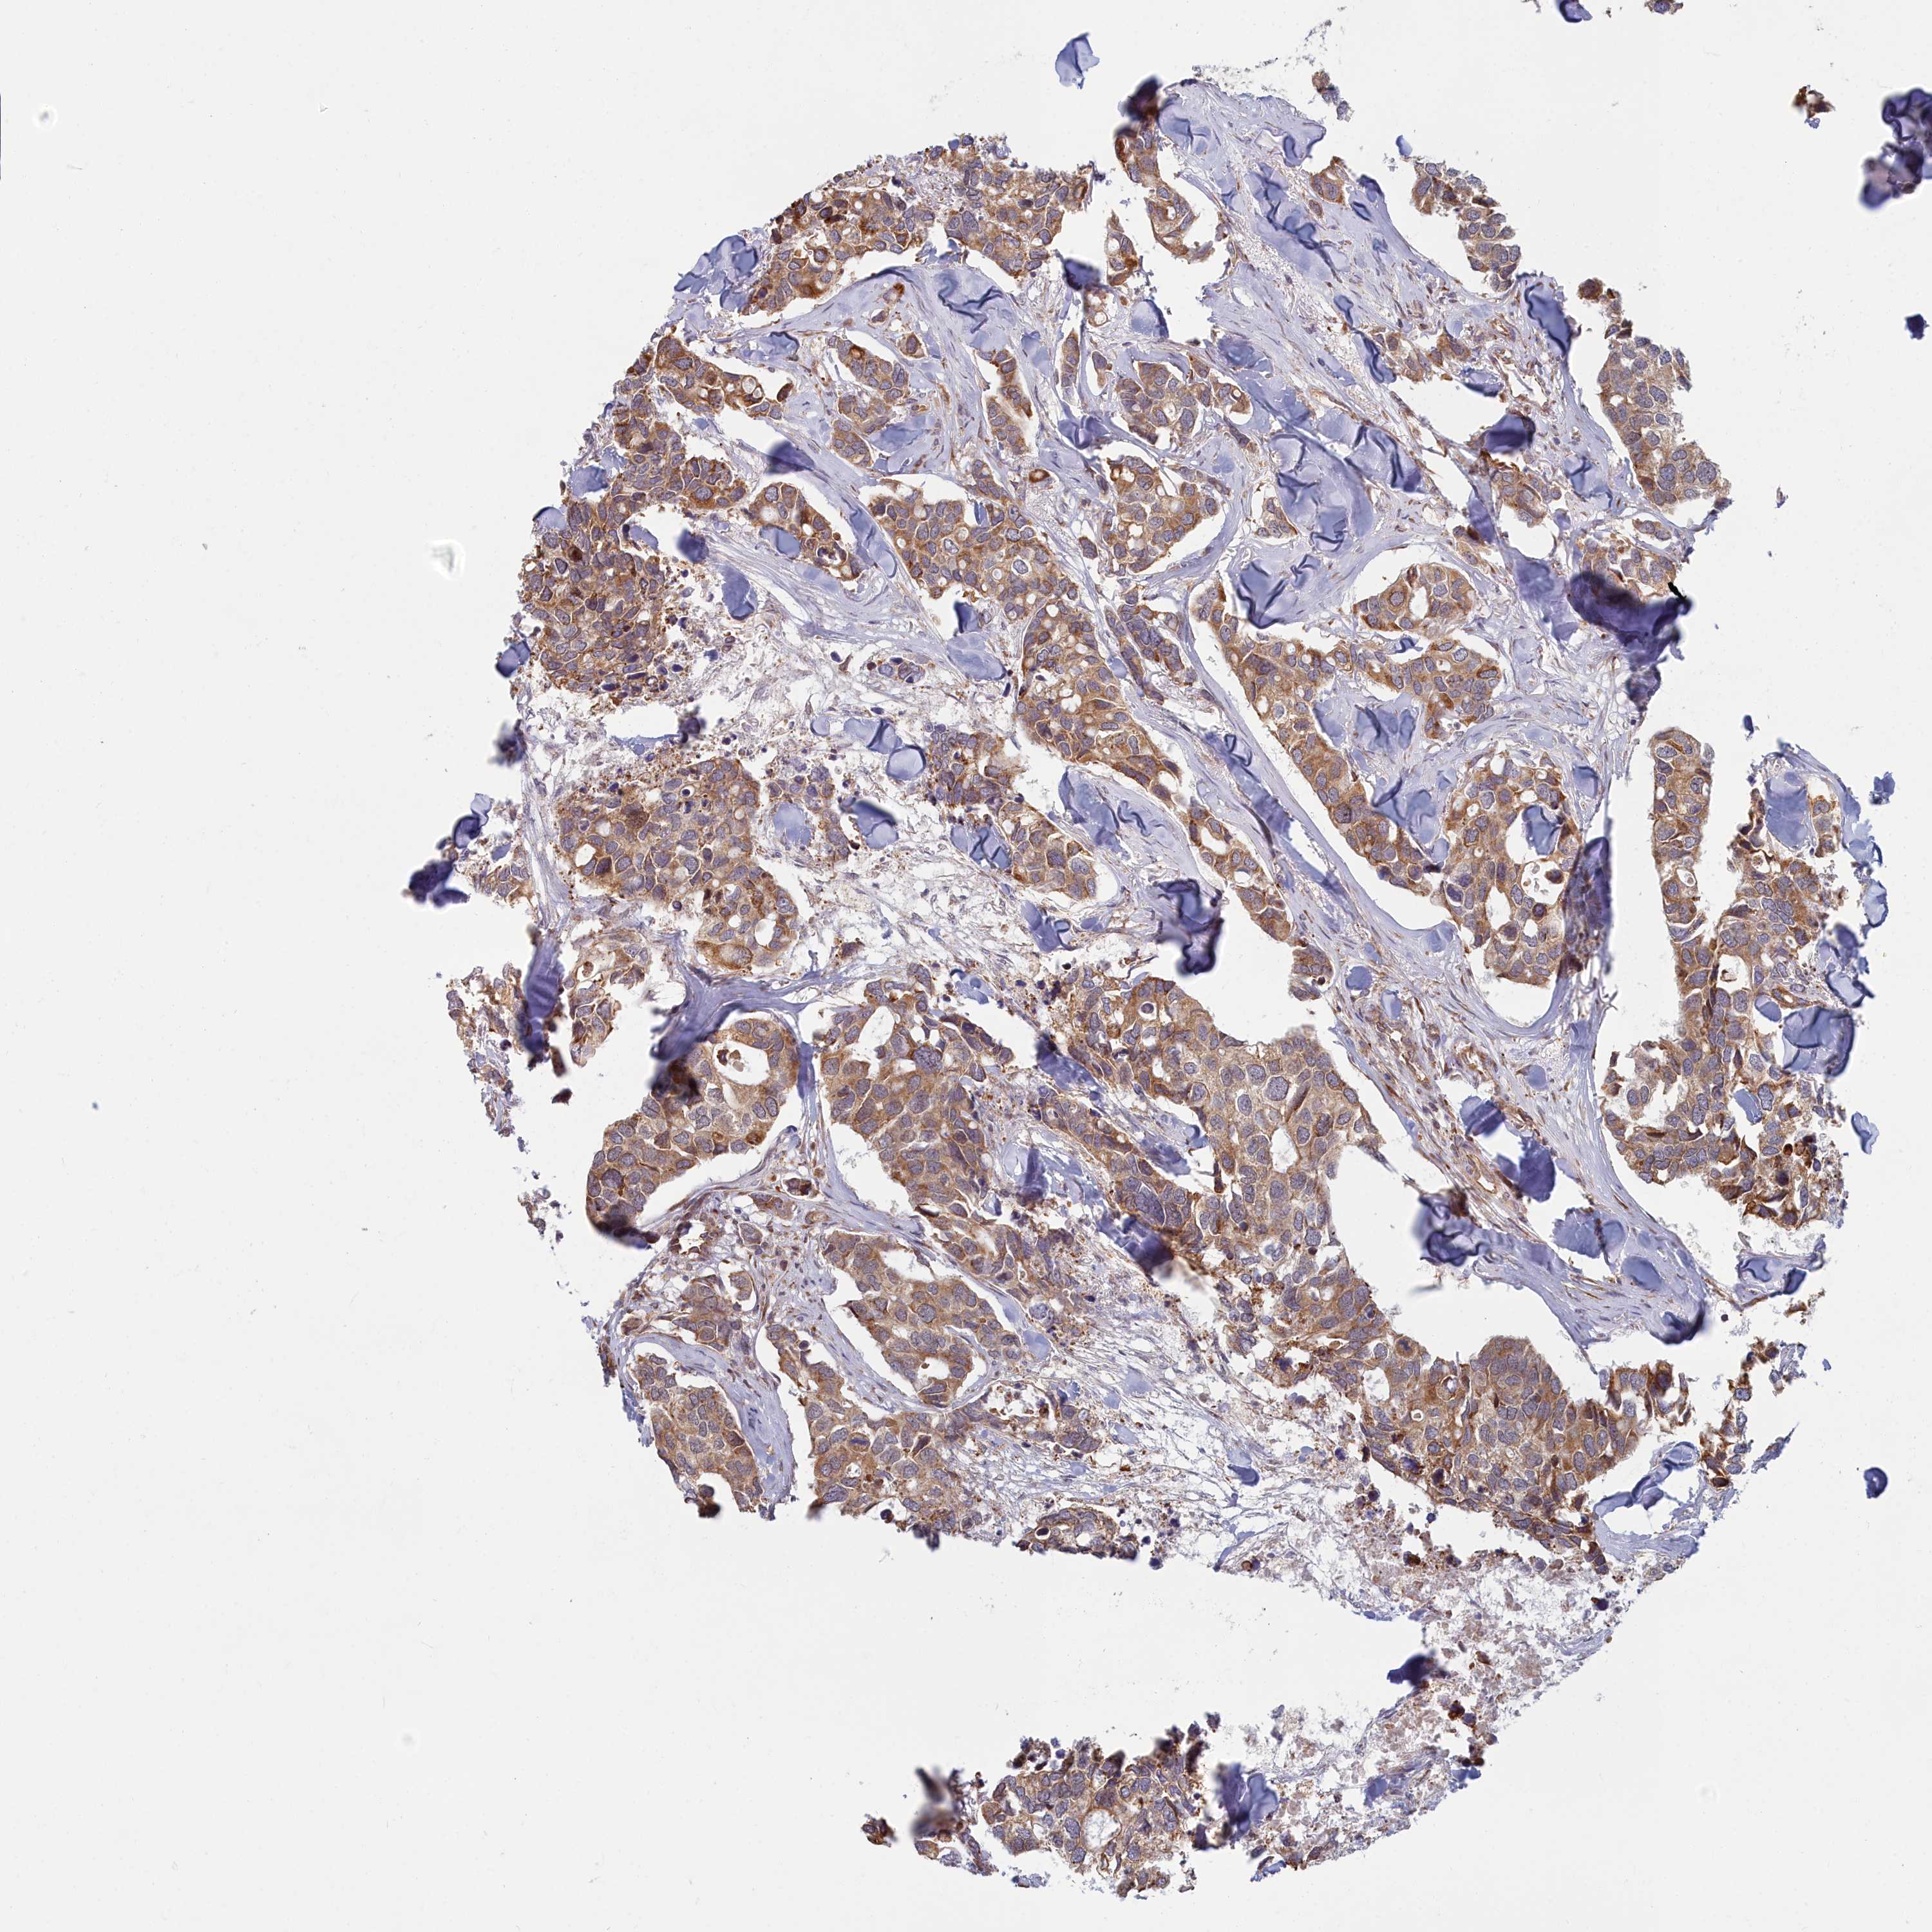

CANCER BREAST CANCER Show tissue menu

BRCA TCGA BRCA VALIDATION PROTEIN EXPRESSION